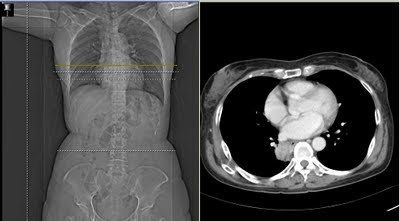

CXR 胸部x光判讀 hiatal hernia

Hiatal hernia (Paraesophageal hernia)

Type 1 sliding hernia, type 2 paraesophageal hernia, type 3 mixed, type 4 massive

Type 1: reflux related medical treatment

Type 2: no medical treatment